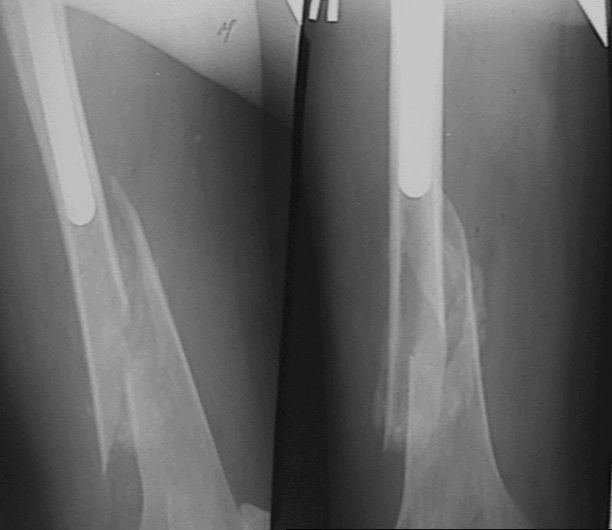

Перелом бедра с эндопротезом

Больной оперирован в конце марта 2003 НИИТО г. Новосибирск. Не замечен перелом бедра р-ма 1.- 2 . (сделанных в НИИТО).

Больному рекомендовали ходить приступая на конечность, отмечает усиление болей, появление укорочения. На контрольных рентгенограммах 19.05.03 рис 3 имеется перелом бедра со смещением, появлением периостальной мозоли. Больной ходит на костылях, приступая на конечность. Сгибание в т\б суставе 90 гр , сгибание в коленном суставе до 90 гр в положении стоя на костылях. Есть несколько вариантов. 1. Провести открытую репозицию фиксацию пластиной с проведением винтов на уровне ножки протеза через кортикальный слой. 2.Провести открытую репозицию фиксацию винтами с межфрагментарной компрессией. Думаем, как выполнить репозицию перелома по длине. 3. Наложить кокситную повязку до окончательного сращения перелома 4. Провести скелетное вытяжение репозицию. Сергей Зырянов Новосибирская область г. Куйбышев ЦРБ